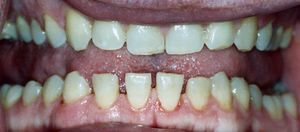

| Facial aspect of a patient with acromegaly. The nose is widened and thickened, the cheekbones are obvious, the forehead bulges, the lips are thick and the facial lines are marked. The forehead and overlying skin is thickened, which may lead to frontal bossing (an unusually prominent forehead sometimes with a heavy brow ridge). | |

تضخم الأطراف Acromegaly هى حالة ينَتجُ عنها تمدد في عظام الوجه والقدمين واليدين. ومعظم حالات تضخم الأَطراف يُسبِّبها تورم الغدَّة النُّخاميَّة، وتحدث عند الأَشخاص ذوي الطول الطبيعي.